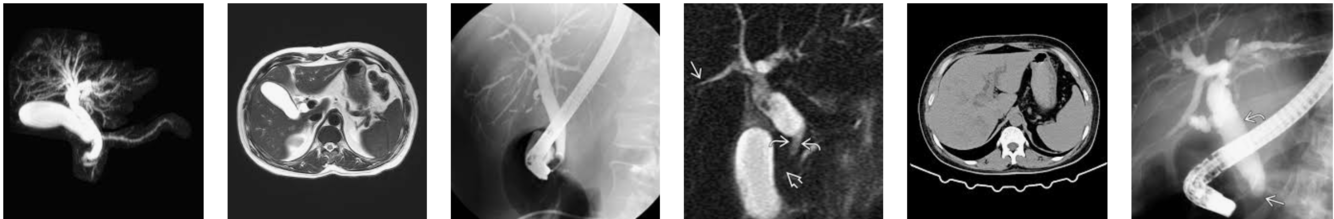

Dilated ducts Dx

Dx?

Biliary MR

Choledochal cysts

Biliary anatomical variants